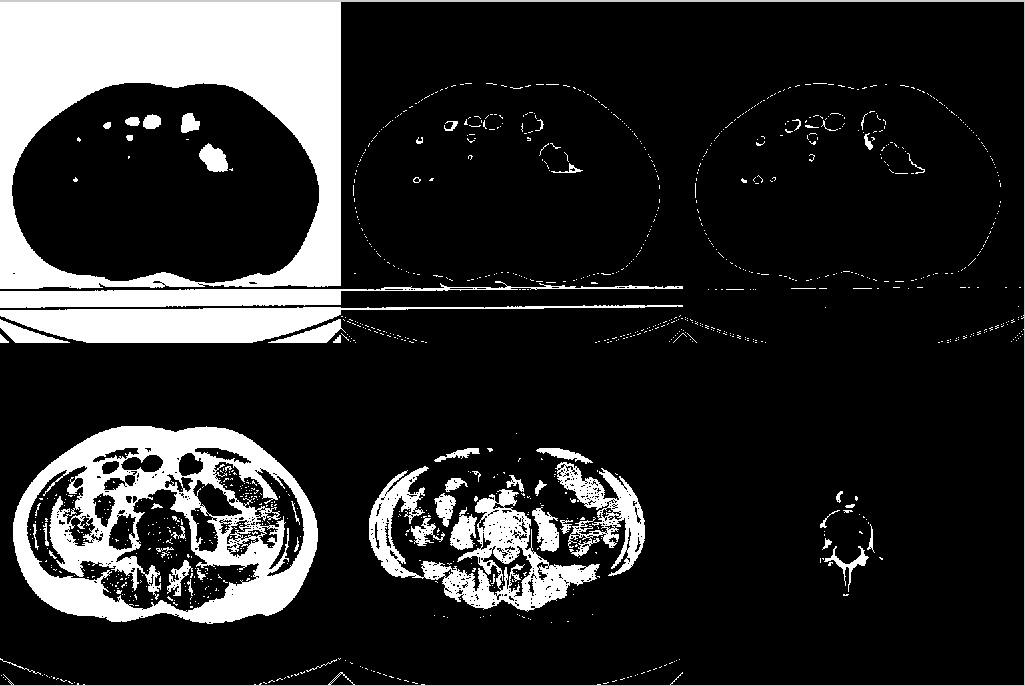

In this seminar we review some standard techniques for image enhancement (via intensity transforms) and morphological operations on images.

The scope of image enhancement is to make the image more suitable for further processing. In our case, we are interested in enhancement for tasks like segmentation and registration of medical images.

We will show how to perform these operations in Matlab for some datasets using Matlab's image processing tool box.